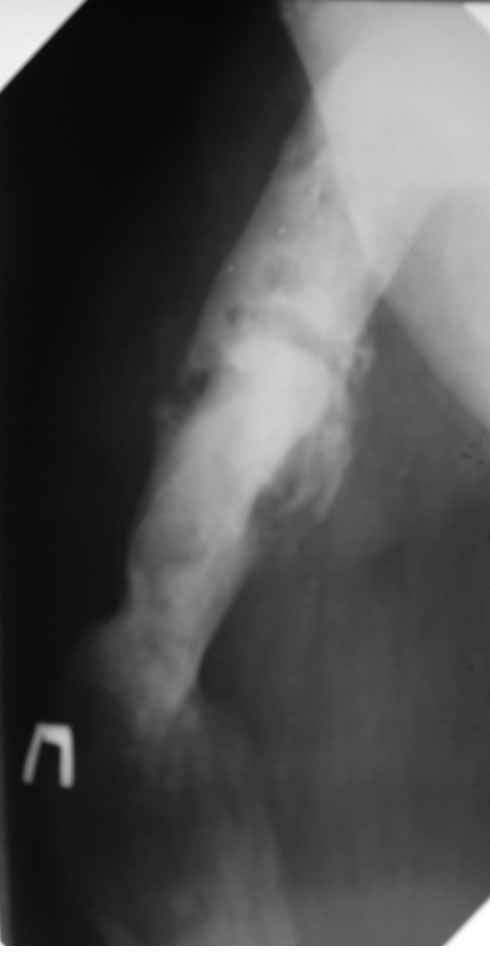

Пациент 29 лет. Неоднократно оперированная Coxa Vara.

В анамнезе этапные операции по поводу устранения Coxa Vara, формирование артродеза коленного сустава, удлинения бедра. В данный момент беспокоит укорочение 7 см, эквинус стопы. Объективно: - местный статус виден на фото, сосудистых и неврологических расстройств нет. Обратился в консультативном порядке, настроен на удлинение голени в г.Волгограде. (со слов больного - не берут без санации очага на голени). Ваши предложения? Из кулуарных соображений - а не актиномикоз ли это? Иссечение рубцов+ VAC+ Стержень с аппаратом + микрососудистый трансплантат(?)

Ваш вопрос, коллега, вполне правомерен. В советское время те из нас, кто занимался костно-гнойной инфекцией видели достаточное количество подобных несчастных, кочующих из стационара в стационар. Своеобразный госпитализм приводил к тому, что люди тратили всю свою, как правило достаточно короткую жизнь, на лечение зачастую реально неизлечимых процессов. В данном случае имеющаяся рентгенологическая картина груботрабекулярной перестройки кости, сочетающаяся с участками склероза говорит, скорее всего, о том, что вся имеющаяся картина, дополненная чудесными фотографиями,вполне укладывается в клинику гематогенного остеомиелита, которым и страдает пациент с детства. Никакие санации, к сожалению, не приведут в данном случае к излечению, так как все имеющиеся рубцы являются зоной жизни этой самой инфекции. При продолжении лечения не исключено достаточно раннее развитие амилоидоза в этом случае. Мне кажется, что оптимальным было бы определить пациента в институт протезирования и протезостроения или в то учреждение, которое в регионе выполняет данную функцию. Специалисты помогли бы определиться с уровнем ампутации, являющейся, по сути, единственным способом разорвть порочный круг и дать пациенту возможность какой-то социальной адаптации. А в плановом порядке, насколько мне известно, можно добиться неплохого финансового обеспечения под протез конечности по квоте. Другого решения здесь нет. С уважением, Андрей Волна

извините за очепятку - не берут без санации очага на бедре. Сейчас имеется отделяемое из нижнего свища с периодическим выходом секвестром в виде мелкой крошки. Движений в ТБС почти нет - есть только сгибание градусов до 10. В стопе - только качательные.

Чтобы пытаться провести лечение данного пациента надо точно понимать - что хочет пациент? Какими усилиями с его и врачей стороны? В какой временной промежуток?. Предложение Андрея Волны возможно, если пациент уже ничего не хочет, или не возможно ему помочь по причине органной недостаточности - амилоидоз. Тогда, конечно, ампутация, протезирование. Возможно, на западе в том числе по экономическим причинам так и поступают. Но судя по литературе далеко не всегда. Эта тактика напоминает известное выражение "Есть человек, есть проблемы,..." ну и так далее. Если пытаться помочь пациенту, то гематогенный остеомиелит не настолько неразрешимая проблема. Хотя не понятно, почему удлинение за счет голени, при ложном суставе бедра. Я бы начал с попытки сращения бедренной кости, любыми возможными на взгляд лечащего хирурга методами (возможно придется их менять по ходу лечения или комбинировать). При мелких секвестрах удаление оных, но в первую очередь создать опорную конечность. Вторым этапом. Купирование гнойного процесса в тех очагах где он остался. При этом, кроме стандартных остеонекрэктомий с дренированием, можно и с VAC (мода вещь великая, а, может, и реально помогает, своего опыта, к сожалению, в применении современного VAC не имею, хотя, мне кажется, в основе это давно известные методы, изложенные у М.Кузина в "Гнойной хирургии"), кроме стандартных остеонекрэктомий необходима пересадка большого сальника в область гематогенного гнойного процесса. Пересадку можно сделать как свободным лоскутом, так и возвожна раскройка его в длинный кровоснабжаемый лоскут и с протягиванием под паховой складкой и распластыванием в зонах гнойных очагов бедра и голени. При наличии организационно нескольких бригад хирургов и подготовленных анестезиологов можно совместить оба этапа (операция может занять до 16 часов). Пересадка большого сальника в зону гематогенного гнойного очага в кости практически дает выздоровление или стойкую ремиссию ( проверено на полифокальных и монофокальных гематогенных остеомиелитах). Далее удлинять конечность в каком угодно месте, но я бы стал делать дистальнее, тем более что это может потребовать, во-первых, неоднократных остеотомий, во вторых, имеется потерянная иннервация малоберцовым нервом (говорится об укорочении 7 см и об эквинусе), и можно совместить удлинение с решением проблемы эквинуса. Это общий план. Надо принять во внимание, что по моему опыту это может потребовать до 8 лет перманентного оперативного лечения в худшем случае. Не все пациенты и врачи готовы к такому марафону. Но опять же по моему опыту, пересадка сальника в зону гематогенного патологического очага давала стойкую ремиссию. У меня был один пациент который после пересадки сальника через 3 года сломал голень с гематогенным очагом - криминальная травма- но гематогенный остеомиелит не обострился, а перелом голени срастался в обычные сроки в гипсе (4-6 мес). Но вернуться к теме ампутации можно на любом этапе. Кстати, надо будет при этом понять на каком уровне ампутировать. Ну и конечно, надо помнить о болезнях культей, в нашем случае это очень возможно (в Новокузнецком институте протезирования было даже отделение болезней культей, в том числе и гнойных). Это как в эндопротезировании суставов - решаем одну проблему, но можем получить другую. С уважением Ангельский А.А.